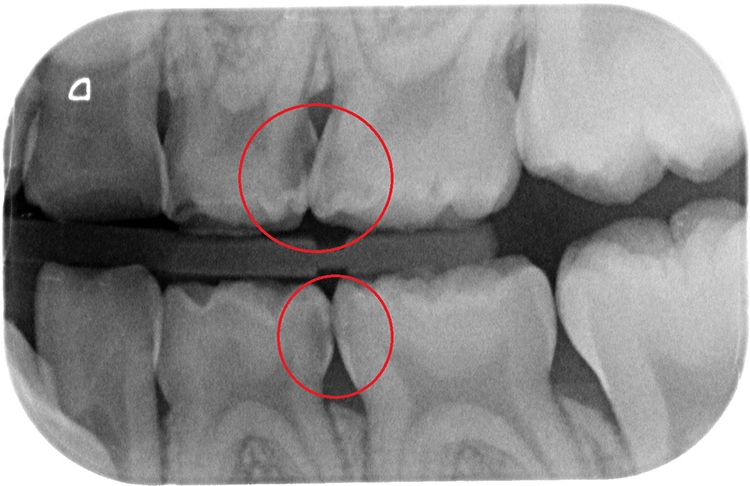

Ein 4-jähriges mäßig kooperatives Kind erscheint zur Kontrolle in der Zahnarztpraxis. Bei der klinischen Untersuchung sind offensichtlich zwei (scheinbar kleinere) approximal kavitierte kariöse Läsionen im Unterkiefer zu sehen sowie Läsionen an den Oberkieferschneidezähnen (Abb. 1a und b). Eine Versorgung dieser Zähne scheint nach klinischer Untersuchung bei diesem Kind noch ambulant möglich.

Erst eine weitergehende röntgenologische Untersuchung zeigt das ganze Ausmaß des Kariesbefalls (Abb. 1c). Das Kind wies an fast allen Milchzähnen bereits Dentinkaries, zum Teil auch schon sehr tiefe Läsionen (Zahn 75), auf. Solch ein Befund scheint bei zahlreichen konventionell-restaurativen Maßnahmen bei altersentsprechender mäßiger Kooperation (fast) nur in Narkose behandelbar.